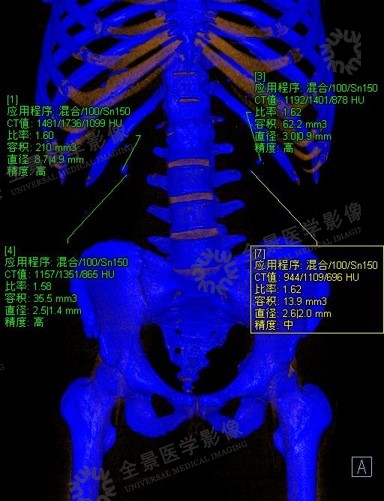

后处理结果会显示肾结石的一些参数,如高低能量下的CT值,比率,结石的体积,直径以及评估的精度:

该例患者为尿酸结石,显示为橘红色,可以通过药物溶石。

位于实线上方的结石被标记为蓝色

位于实线下方的结石被标记为橘红色

尿酸结石——橘红色

非尿酸结石——蓝色

结石双能量分析(100kv/150kv)示:双肾肾盂内多发结石,均标记为蓝色。左肾数枚小结石呈颗粒状,大者大小约2.6mm×2.3mm,体积13.9mm3,CT比值1.53(双能量指数)。右肾数枚结石,大者大小约8.7mm×4.9mm,体积210mm3,CT比值1.6(双能量指数)。

双能量结石成分分析为双肾多发羟磷灰石成分结石,非尿酸结石。